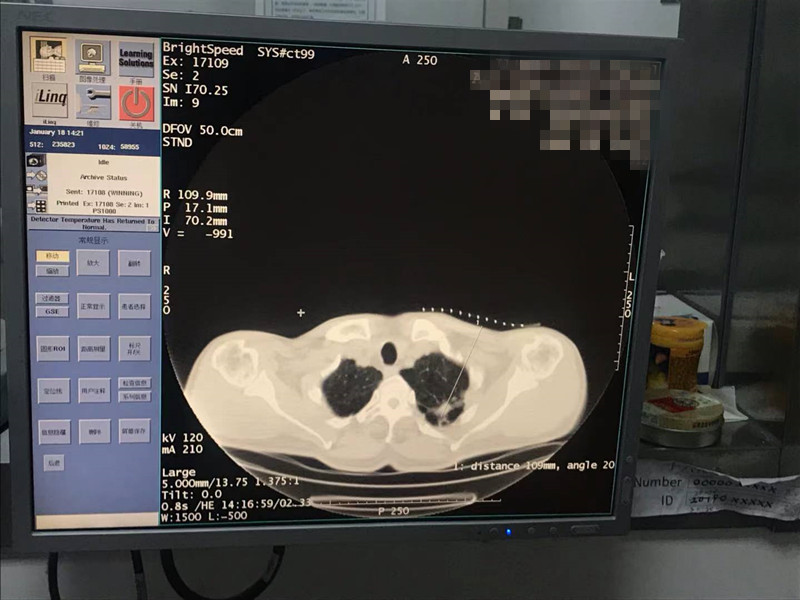

2021年1月份肺部氩氦刀手术